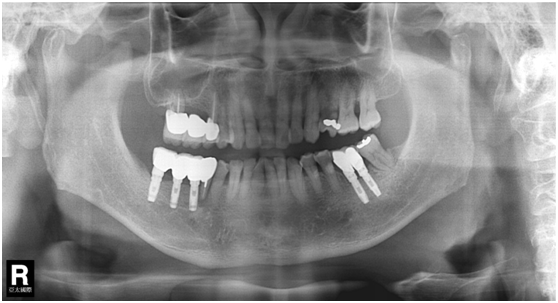

患者的原始片 91/06/13

患者陳先生於91/06/03初診,為一個牙周病患者,合併有右下缺牙。經過保守性牙周處理後,於91/08/14放置右下三顆植體。

完成後大約半年至一年進行一次例行性追蹤檢查,並無特別問題。以下為96/08/13時的追蹤小片,可以見到當時三顆植體的骨高度並無顯著變化。但右下第一小臼齒此時發現有搖動度增加的情形,當時對該顆牙做了咬合調整,降低咬合功能負荷,希望能有所改善。